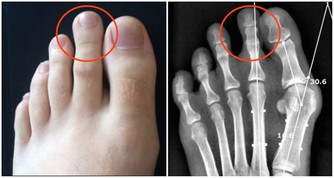

■ 出汗好處3/防治肢體性疾病

其實,「生汗」不僅能排出血液裡的廢物垃圾,稍微增加一點運動量,活動到出汗,還能防治肢體性疾病,如常見的關節炎、關節痠麻沉重、肌肉痛、四肢痙攣等。

有人可能要問,肢體有病還運動,不是往傷口上撒鹽嗎?為什麼運動還能防治關節疾病呢?痛則不通,通則不痛。從中醫角度來講,所有的疼痛疾病,都是由於外邪入侵或身體內部失調,導致氣血淤滯所引發,治療的原則就是疏通經絡,促進氣血流通,而適當的運動,正是疏經活血的最好辦法。

經絡氣血通暢,疼痛就會不治自癒。如果再運動到出汗,侵入經脈的風、寒、濕等病邪垃圾,也會隨著汗液被排除,這就相當於中醫治病的「汗法」,它的作用與吃藥相同。標本兼治,病能不好嗎?